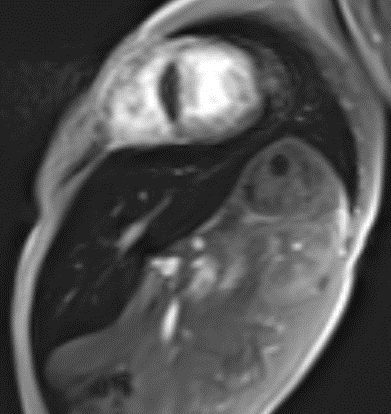

Magnetic resonance imaging (MRI) assessment of liver iron concentration (LIC) is necessary for quantitative staging of iron overload in children with β-Thalassemia. There is no enough evidence about the effect of spirulina therapy on LIC.

To assess LIC by MRI in multitransfused β-Thalassemic children infected with HCV before and after Spirulina Therapy.

Thirty multi-transfused β-thalassemic children infected with HCV, were subjected to clinical evaluation, appropriate laboratory investigations and assessment of LIC by MRI. They were classified according to LIC into mild (group 1) and moderate to severe group (group 2). In addition to standard packed red cell transfusion, Spirulina therapy was given orally for 3 months, after which re-evaluation of these children was performed by repeating the same investigations.

There was significant increase in LIC associated with significant changes in other MRI parameters (significant decrease in T2* and significant increase in R2*) in patients with β-Thalassemia of moderate to severe group as compared to those of the mild group before treatment. The mean values of serum ferritin (SF) was statistically insignificantly higher among patients of mild group. There was no significant correlation between different MRI parameters and SF level. There was negative correlations between LIC and T2* and positive correlation between LIC and R2*. There was significant decrease in values of LIC accompanied with significant improvements in SF after spirulina therapy as compared to their pretreatment values in patients of the moderate to severe group.